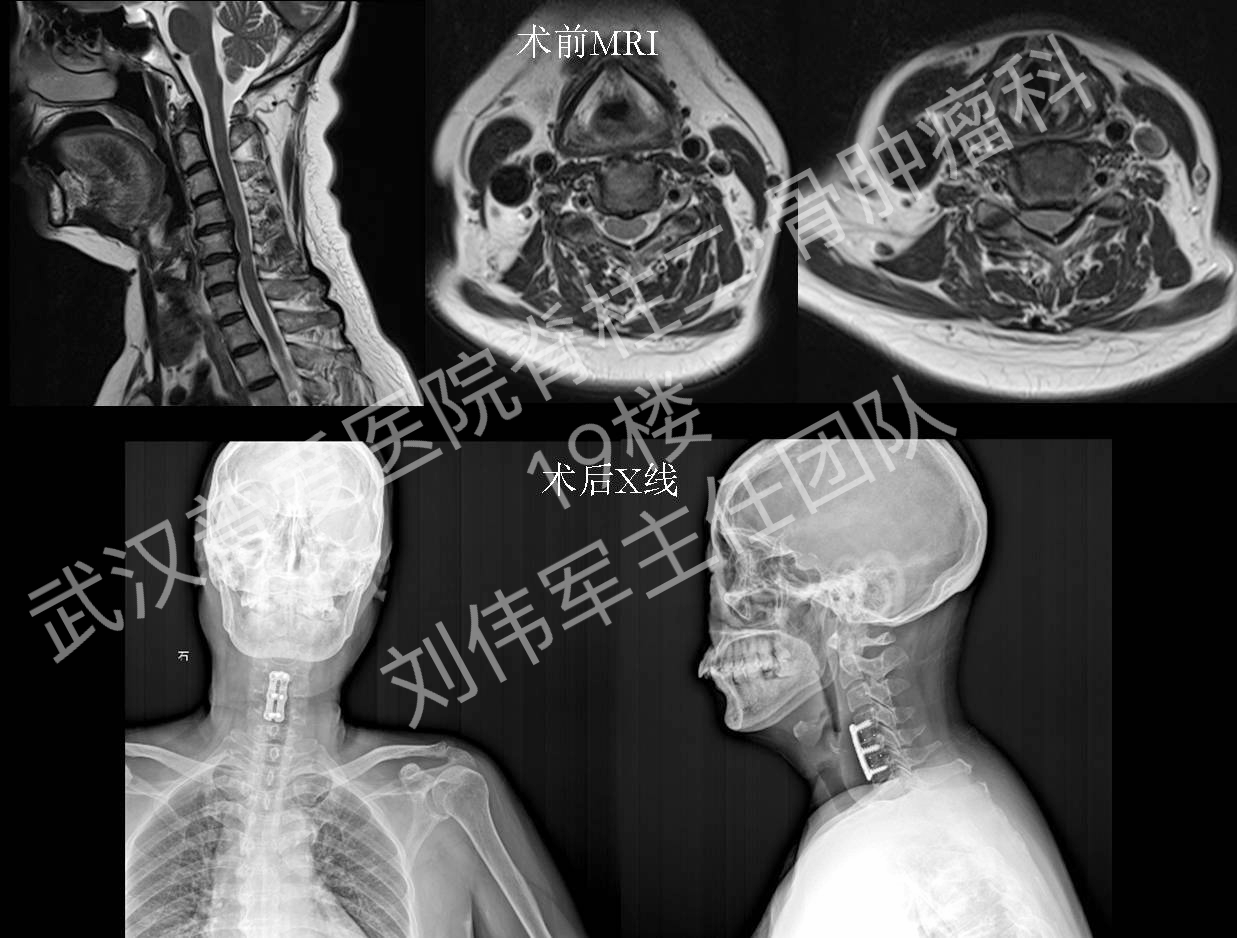

2016年刘主任团队典型病例:脊髓型颈椎病-前路

1237x938 - 628KB - PNG